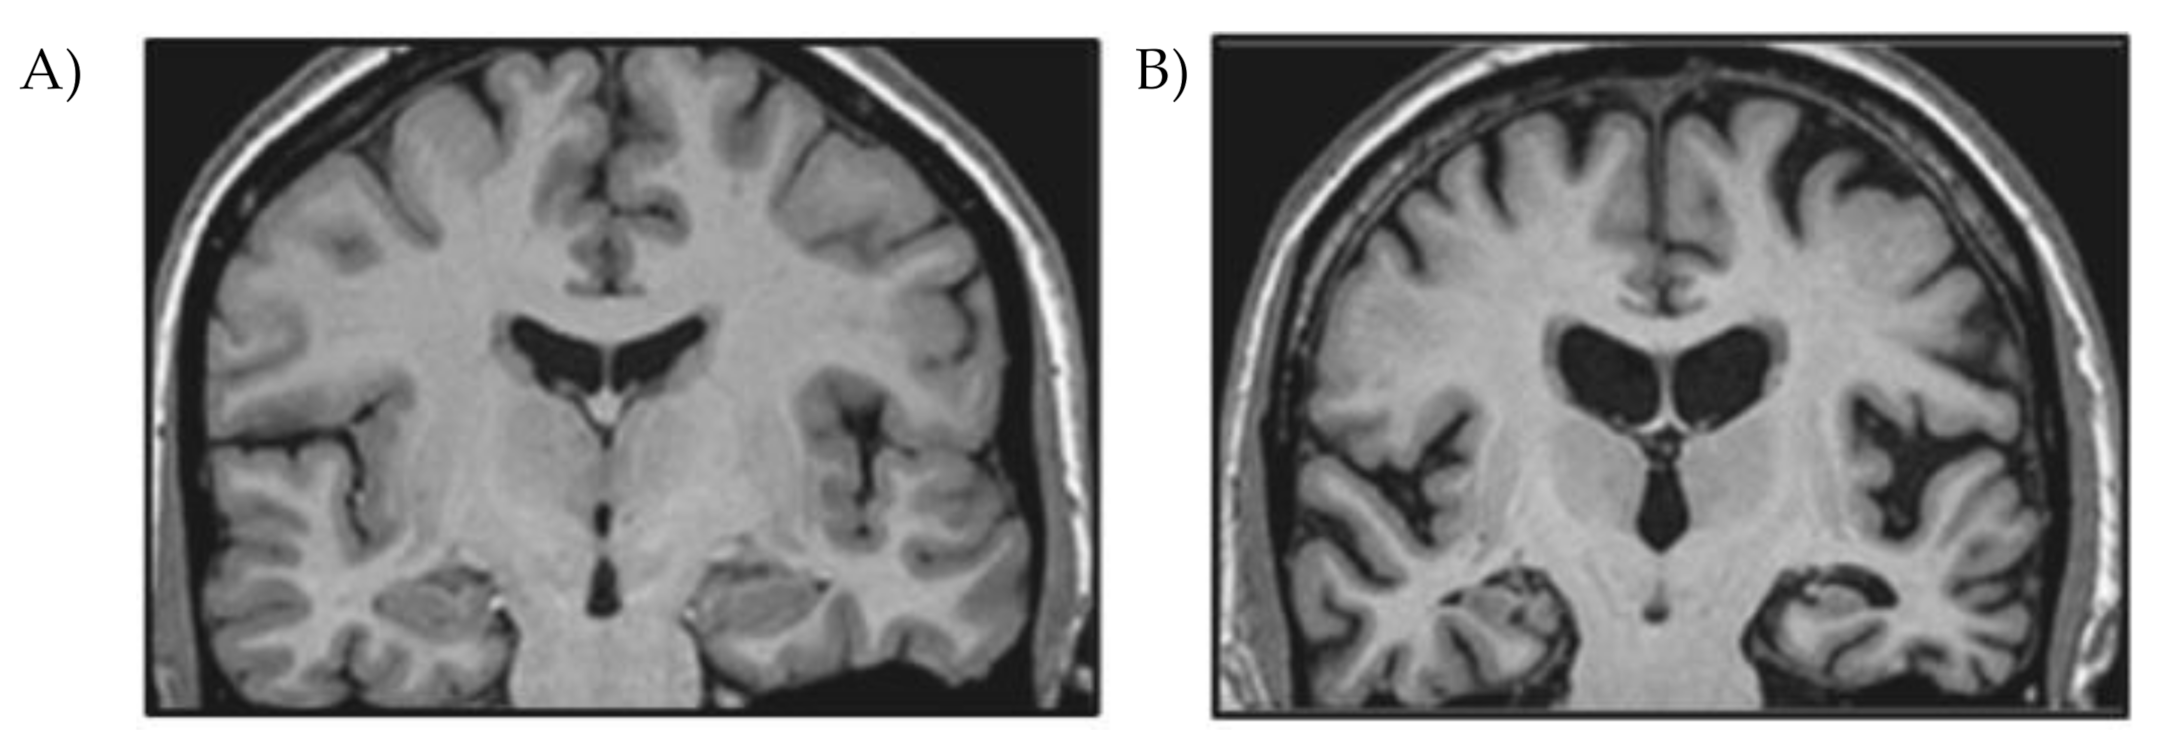

3.2. Neuropathology